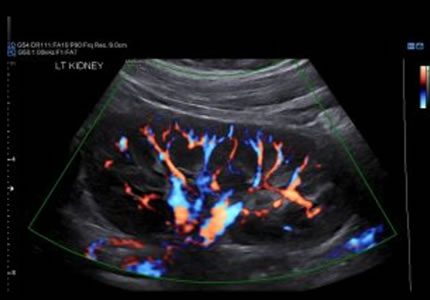

Renal & Urinary Tract

- A comprehensive evaluation of both kidneys to screen for stones, cysts, and structural anomalies. It is an essential investigation for recurrent urinary tract infections (UTIs), "flank" (side) pain, or changes in kidney function.

- A specialist check using Doppler ultrasound to look at the blood flow to the kidneys. This screens for narrowing in the arteries, which can sometimes be an underlying cause of high blood pressure.

- £300

- Ideal for: Investigating secondary causes of high blood pressure.